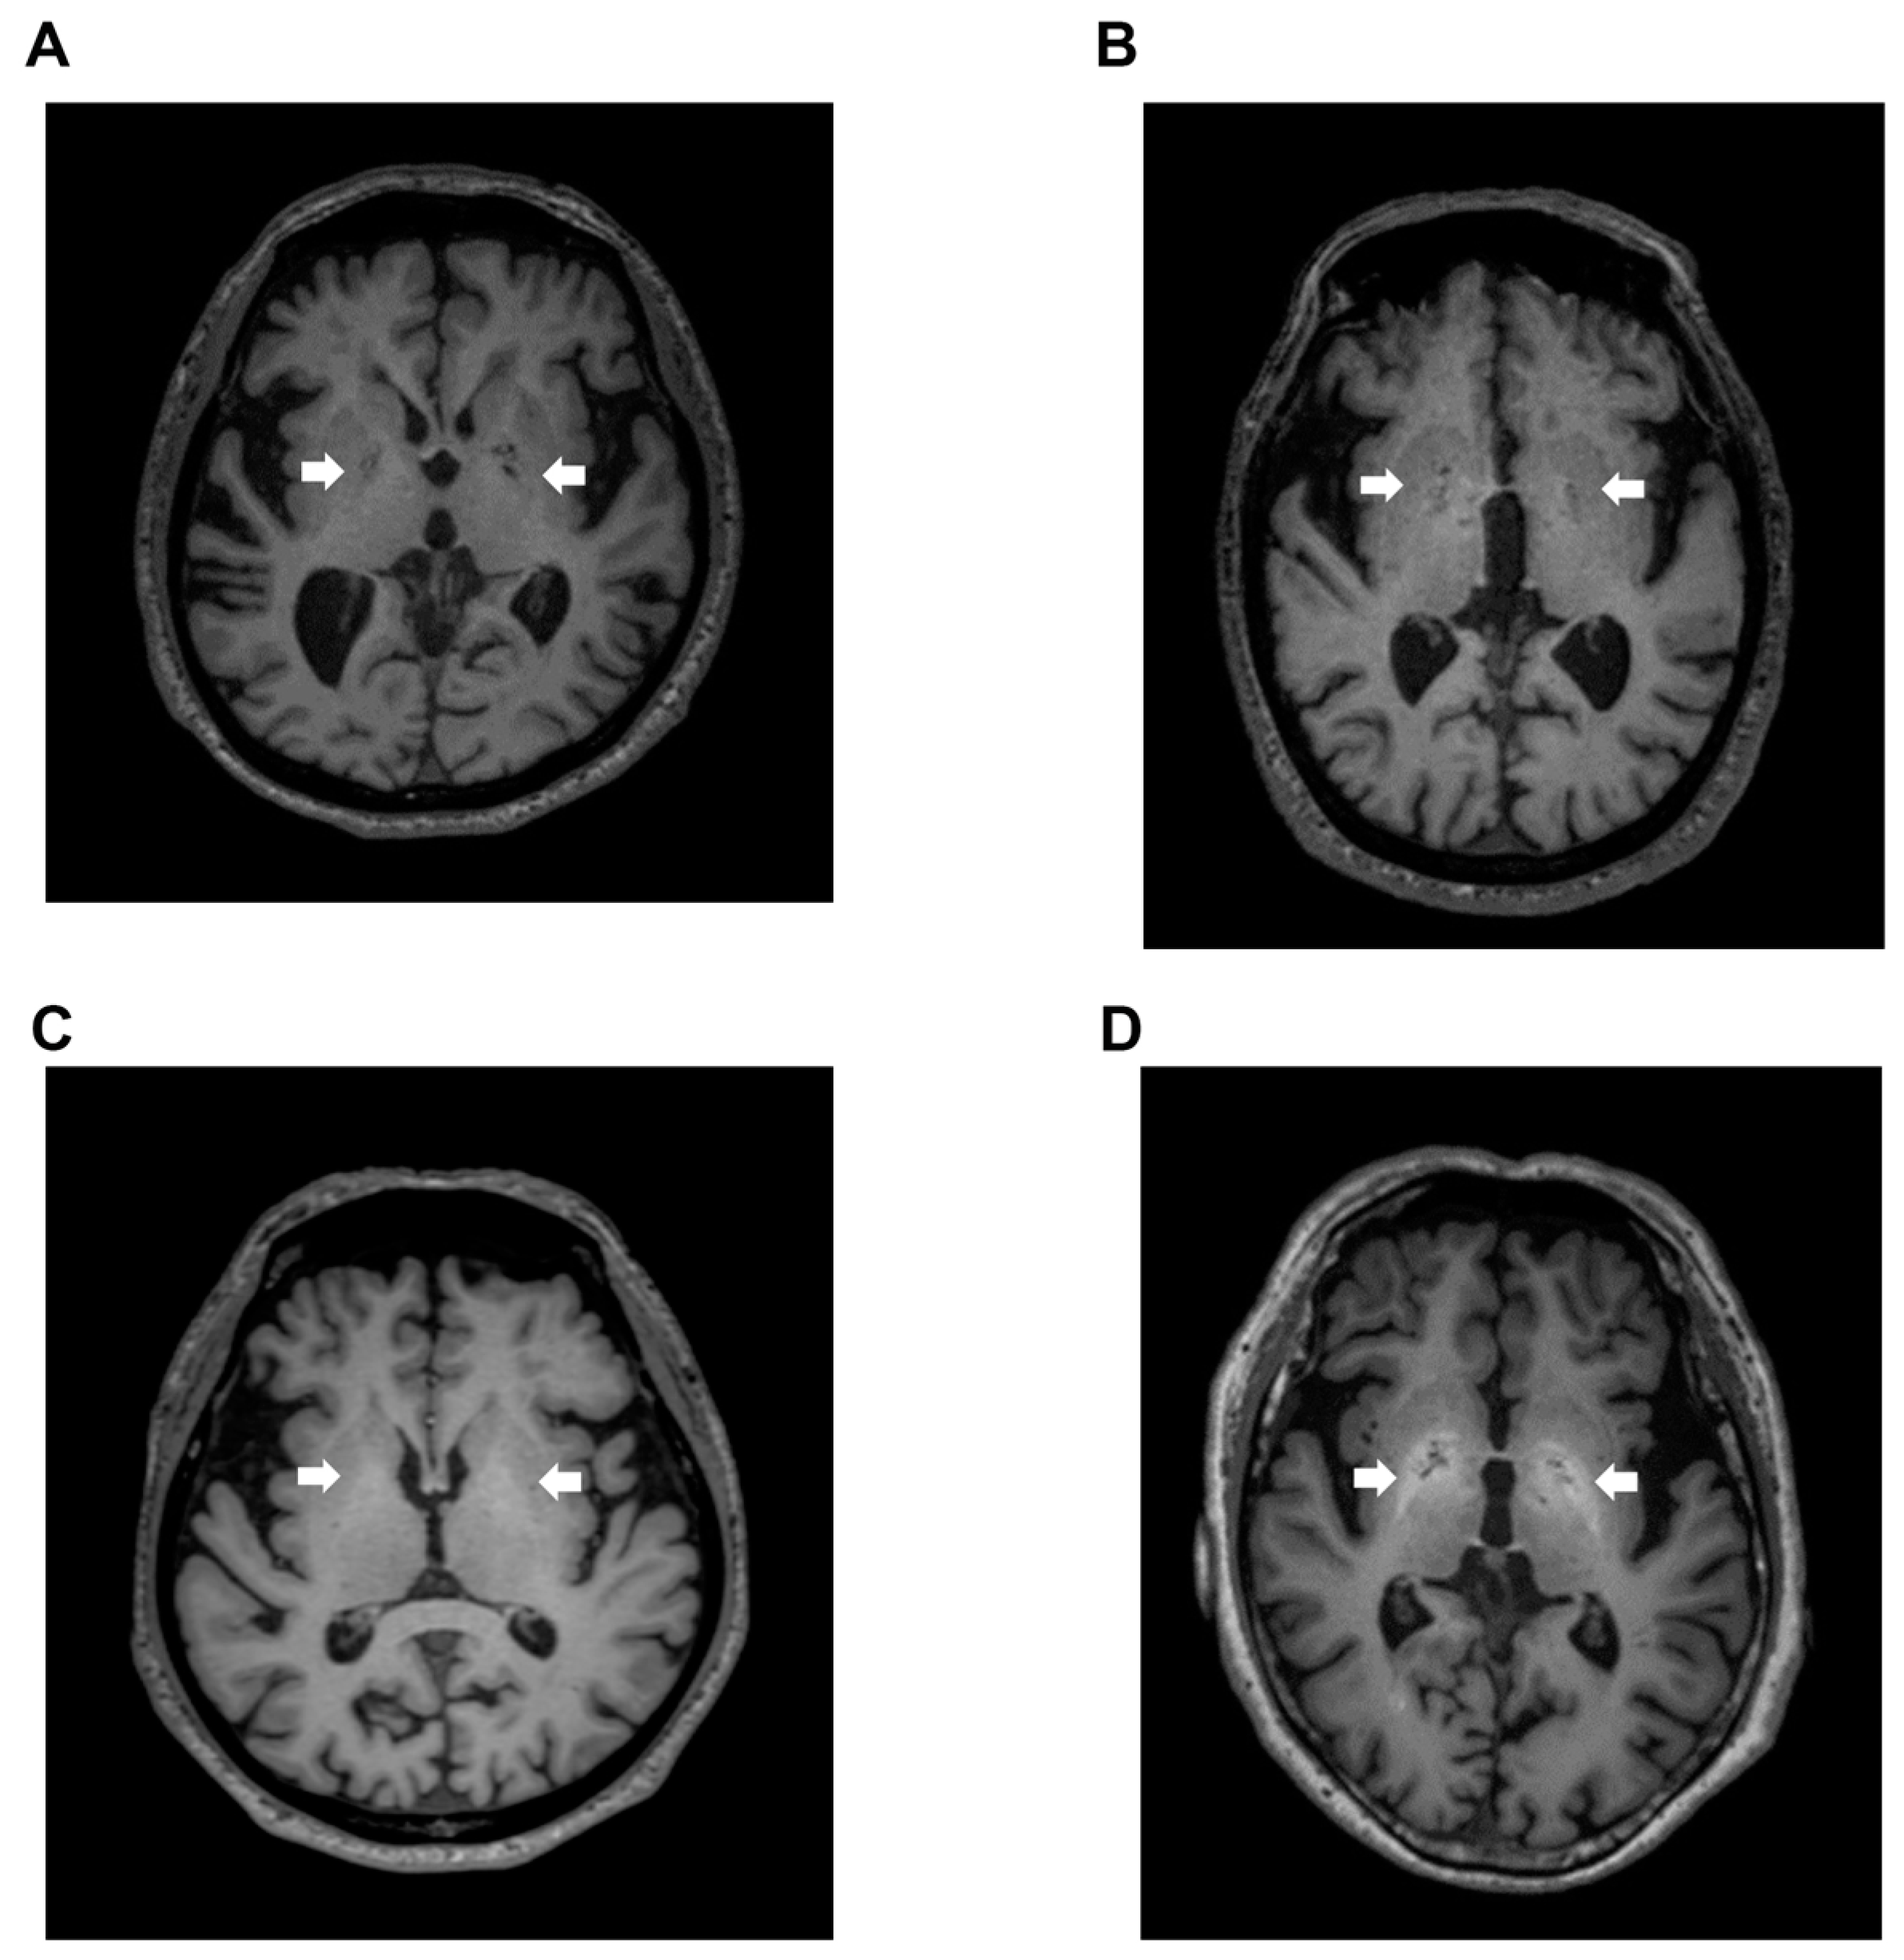

Signal intensity value of GP (arrow) in transverse T1-weighted imaging was mildly increased (Figure 2B,C) or clearly increased (Figure 2D) on a case-by-case basis, when compared to healthy subject (Figure 2A). Indeed, the signal intensity of GP in LC patients with HE was dramatically increased compared to the values seen in LC patients without HE (p < 0.05), healthy subjects (p < 0.05), and dementia patients (p < 0.001). Contrarily, the signal intensity of GP observed in dementia patients was markedly decreased when compared to those seen in LC patients with HE (p < 0.001), LC patients without HE (p < 0.001), and healthy subjects (p < 0.05) (Figure 3).

Figure 2.

T1-weighted images. (A) Transverse T1-weighted imaging from a 74-year-old healthy subject. Signal intensity value of GP (arrow) was 0.952, which is below the cut-off value of 0.994; (B) Transverse T1-weighted imaging from a 79-year-old LC patient. Signal intensity value of GP (arrow) was 0.992, also below the cut-off value of 0.994; (C) Transverse T1-weighted imaging from a 63-year-old LC patient. Signal intensity value of GP (arrow) was 1.006, which exceeded the cut-off value of 0.994; (D) Transverse T1-weighted imaging from a 68-year-old HE patient. Signal intensity value of GP (arrow) was 1.024, also exceeding the cut-off value of 0.994. GP, globus pallidus; LC, liver cirrhosis; HE, hepatic encephalopathy.